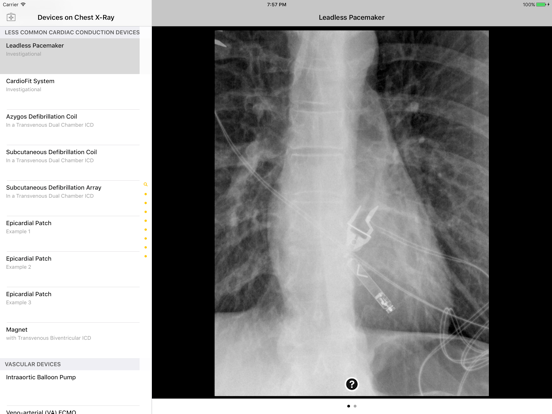

Introducing the Atlas of Medical Devices on Chest Radiography – one of the largest and most comprehensive collections of medical devices on chest radiography in existence. This app is an outstanding resource for physicians, physicians-in-training, and many healthcare providers who encounter medical devices on chest x-rays in daily practice. Review and explore the appearances of common and uncommon medical devices, organized by category. Search for a medical device in seconds using this app's lightning quick search feature.

· Countless images, organized into the following categories: Common Cardiac Conduction Devices, Less Common Cardiac Conduction Devices, Vascular Devices, Airway Devices, Enteric Devices, Neurological Devices, Musculoskeletal Devices, and Miscellanenous Devices.

· Tap the caption icon to read more about the device and to see it highlighted on the chest radiograph.